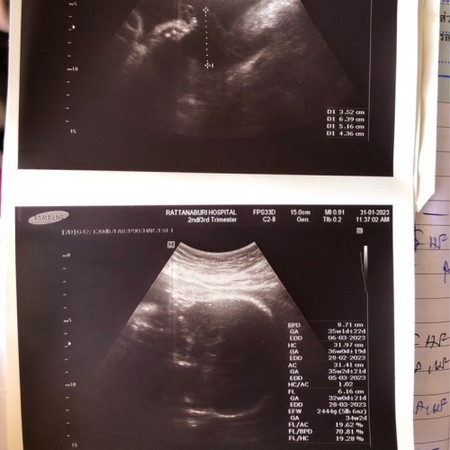

ไปหาหมอตอน32/2วีค

คุณหมอบอกว่าเด็กน้ำหนักเยอะมากกกกกก แล้วน้ำหนักแม่ก็ขึ้นเยอะเช่นกัน วันนี้ตรวจน้ำตาลได้81/84/64หมอให้งดหวานแต่น้ำตาลต่ำควรทานอาหารประเภทไหนดีค่ะ

พอกันเลยค่ะ ตอน 32+2วีค น้องหนัก 2312 กรัม น้ำหนักเกินเกณฑ์ น้ำตาลแม่ 138 ต้องฉีดอินซูลินทุกวันค่ะ ตอนนี้ 36 วีค รอลุ้นน้ำหนักน้องวันอาทิตย์ค่ะ